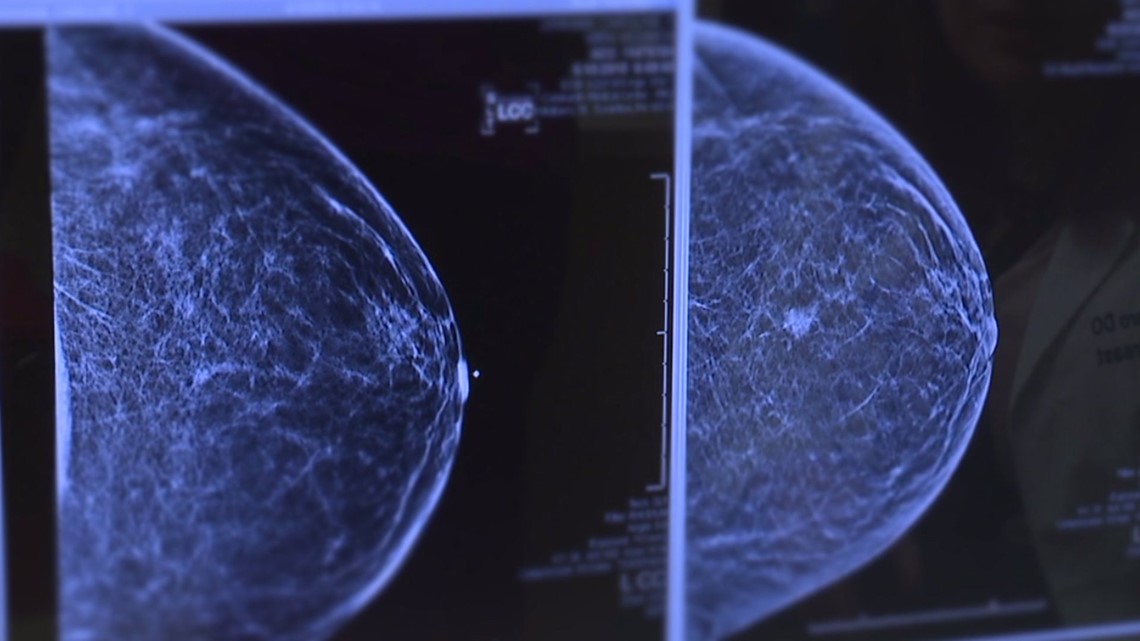

Google’s AI breast cancer screening tool is learning to generalize

Improvement of Cancer Detection on Mammograms via BREAST Test Sets Imaging Tests For Breast Cancer Your doctor will talk with you about which. You may be referred to a breast clinic if a gp thinks you have possible breast cancer symptoms that need. Mammography, which is considered the gold standard, and breast ultrasonography are employed as routine imaging modalities. This guideline includes recommendations on: Screening can help to find breast. Referral, diagnosis and preoperative assessment.. Imaging Tests For Breast Cancer.